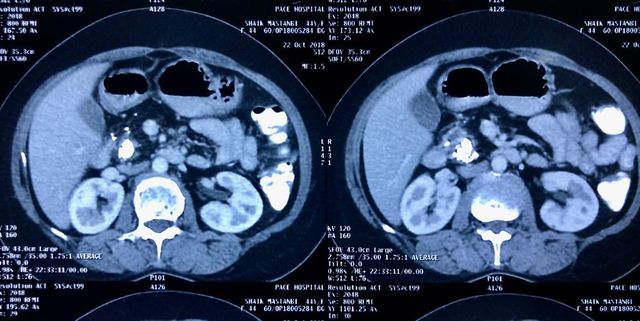

Challenging emergency during the COVID: Child’s A CLD with HUGE gastric varices uncontrolled

Child’s A CLD with HUGE gastric varices uncontrolled by Endoscopic glue and attempted EUS coiling. One salvage option would be TIPSS with balloon vascular occlusion but due to logistics we went for modified sugiura procedure. Splenectomy + Gastro esophageal devascularisation with anterior Gastrotomy and overseeing of gastric varices with pyloroplasty. Images show 1 CECT showing large gastric fundal varices. 2,3,4 Gastro Esophageal devasc 5, 6 Large fundal varices before and after oversewing. 7. Anterior gastrotomy 8. Pyloroplasty. Postoperative recovery was uneventful.